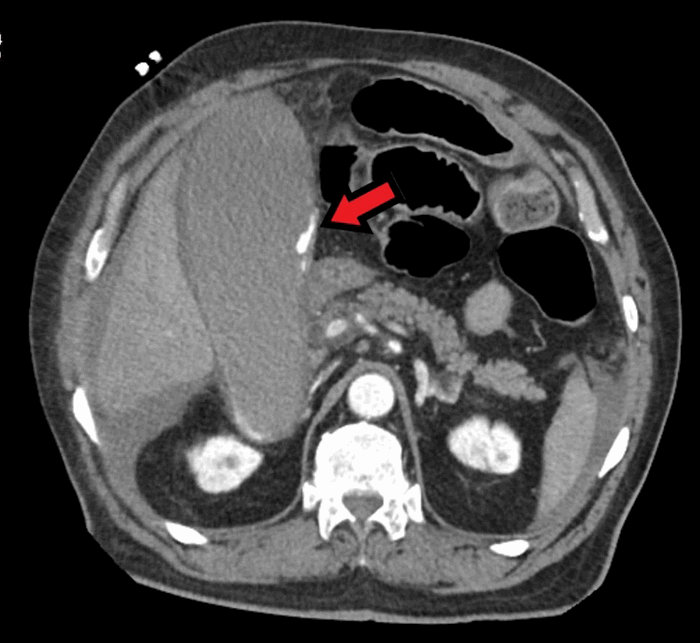

A 68-year-old male with no known history of cholecystitis or biliary disease presented to the emergency department with the complaint of diffuse epigastric pain. His medical history was significant for Roux-en-Y gastric bypass, noninsulin dependent diabetes, hypertension, acid reflux, and coronary artery disease status post a coronary artery bypass graft, for which he takes a daily baby aspirin. At that time, an evaluation for acute coronary syndrome was negative and he was discharged home with pain medication. There was no evaluation for abdominal pathology at this time. Three days later he again presented to the emergency department due to progression of his epigastric pain. At this time a diagnosis of acute cholecystitis was made by ultrasound with incidental finding of ascites (Figure 1). He had a significant leukocytosis (38.7 k/ul) and lactic acidosis (3.2 mg/dL). Given the severity of his illness, further imaging was obtained. A computed tomography (CT) scan demonstrated massively distended gallbladder with a blush of contrast in the lumen of the gallbladder concerning for active hemorrhage (Figure 2), as well as a significant amount of hemoperitoneum (Figure 3). The patient subsequently became hemodynamically unstable and was transported to a quaternary care center. He transiently responded to resuscitation with blood products but ultimately decompensated again before being emergently transported to the operating room. A midline exploratory laparotomy was performed that demonstrated a large amount of blood in the peritoneal cavity. All four quadrants were packed with lap sponges and old blood was evacuated. The bowel appeared to be decompressed. The gallbladder was found to be massively distended and filled with blood. One necrotic area had perforated, and blood was actively spraying into the abdomen. No other sources of bleeding were seen. The gallbladder was sharply opened and packed. A clear source of bleeding was not seen in the gallbladder but was controlled with packing. At this time pulses were lost and cardiac monitor with rhythm strips showed ventricular tachycardia. Despite attempts at resuscitation with advanced cardiac life support protocol, the patient ultimately expired, with a presumptive diagnosis of cardiogenic shock due to acute blood loss. An autopsy was not performed per patient family wishes.

Figure 1. Ultrasound image demonstrating distended gallbladder with thickened wall and ascites. Arrow head shows the distended gallbladder. Arrow shows ascites.

In the cases we reviewed, right upper quadrant ultrasound and CT scan of the abdomen and pelvis were the most common initial imaging studies in these patients. Ultrasound findings include distended gallbladder, wall thickening and pericholecystic fluid collection, with the most frequent diagnosis being acute cholecystitis. One study reported ultrasound finding of an intraluminal pulsatile mass.6 CT scans were performed in 11 patients, with only four of those demonstrating active intraluminal extravasation of contrast.4,5,9 A pseudoaneurysm of the cystic artery was present in three patients.10 Other findings suggestive of hemorrhage on CT scan included hemoperitoneum (one patient), blood clots in gallbladder (one patient), and heterogeneous intraluminal fluid (one patient) were described in three patients. Two patients had no significant CT findings. The initial imaging study of choice for biliary disease is ultrasonography.11 However, ultrasound does not appear to be ideal for differentiating between acute and hemorrhagic cholecystitis. The retrospective review study reported ultrasound findings on 19 acute cholecystitis patients with pathological findings of hemorrhage cholecystitis.12 They reported that ultrasound findings suggesting hemorrhagic cholecystitis included intraluminal membrane, focal gallbladder wall irregularities and nonshadowing, nonlayering intraluminal echoes.12 However, these findings were not present in the other 14 patients we reported here. Notably, because the retrospective study was published in 1987, CT scans might not have been widely available. We conclude that CT scan is useful in the diagnosis of hemorrhagic cholecystitis.